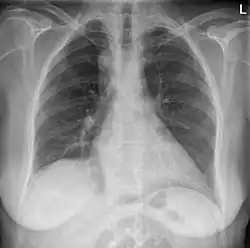

Anterior-posterior chest radiograph showing a right-sided aortic arch

After birth, a right-sided aortic arch is visualized on chest radiography, by the aortic knob (the prominent shadow of the aortic arch) that is located right from the sternum instead of left. Complex lesions are often assessed by MRI or CT.